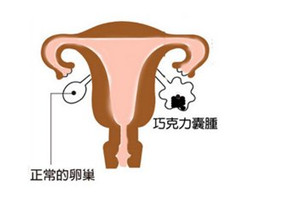

巧克力囊肿是子宫内膜异位症的一种常见类型,子宫腔的异位内膜在卵巢中生长,形成囊肿,因为囊液呈巧克力颜色而得名。

因为是子宫内膜,即使不在子宫腔,它也会受到月经周期雌孕激素波动的影响,来一次月经,就长一点。然后脱落的内膜又不能像月经一样排出,只能呆在囊肿里,越积越多。囊肿越来越大。